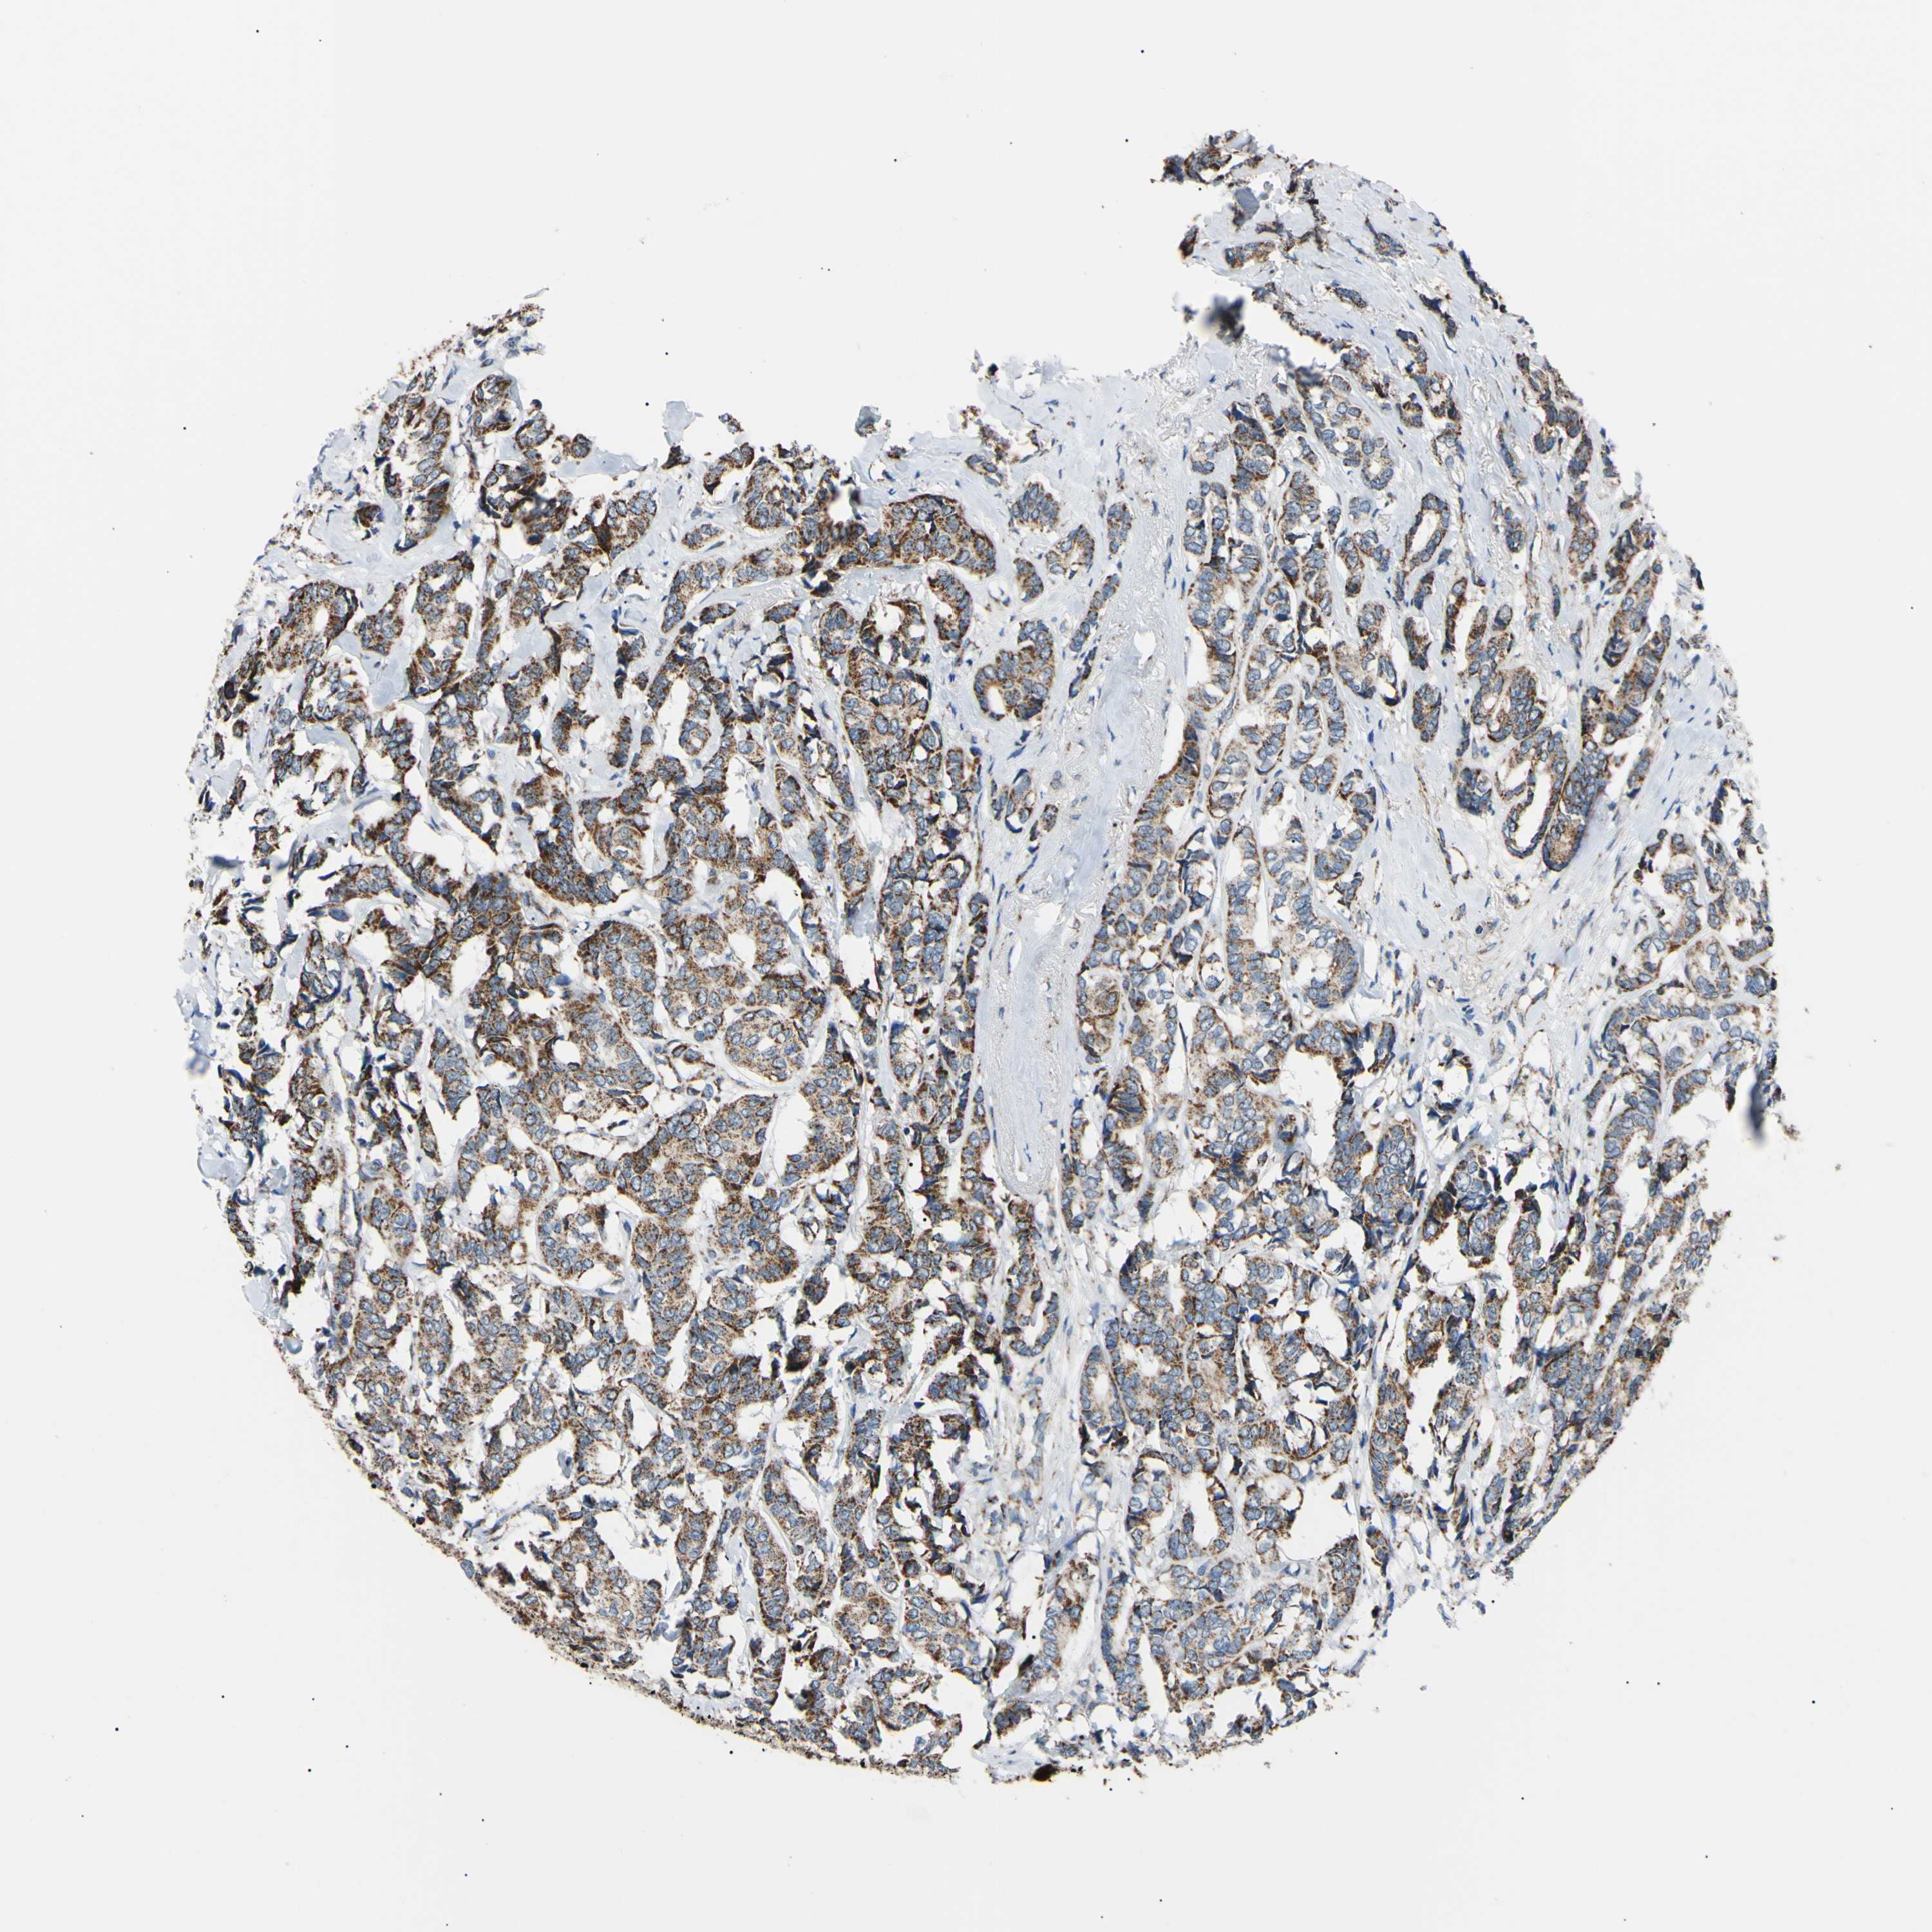

CANCER BREAST CANCER Show tissue menu

BRCA TCGA BRCA VALIDATION PROTEIN EXPRESSION